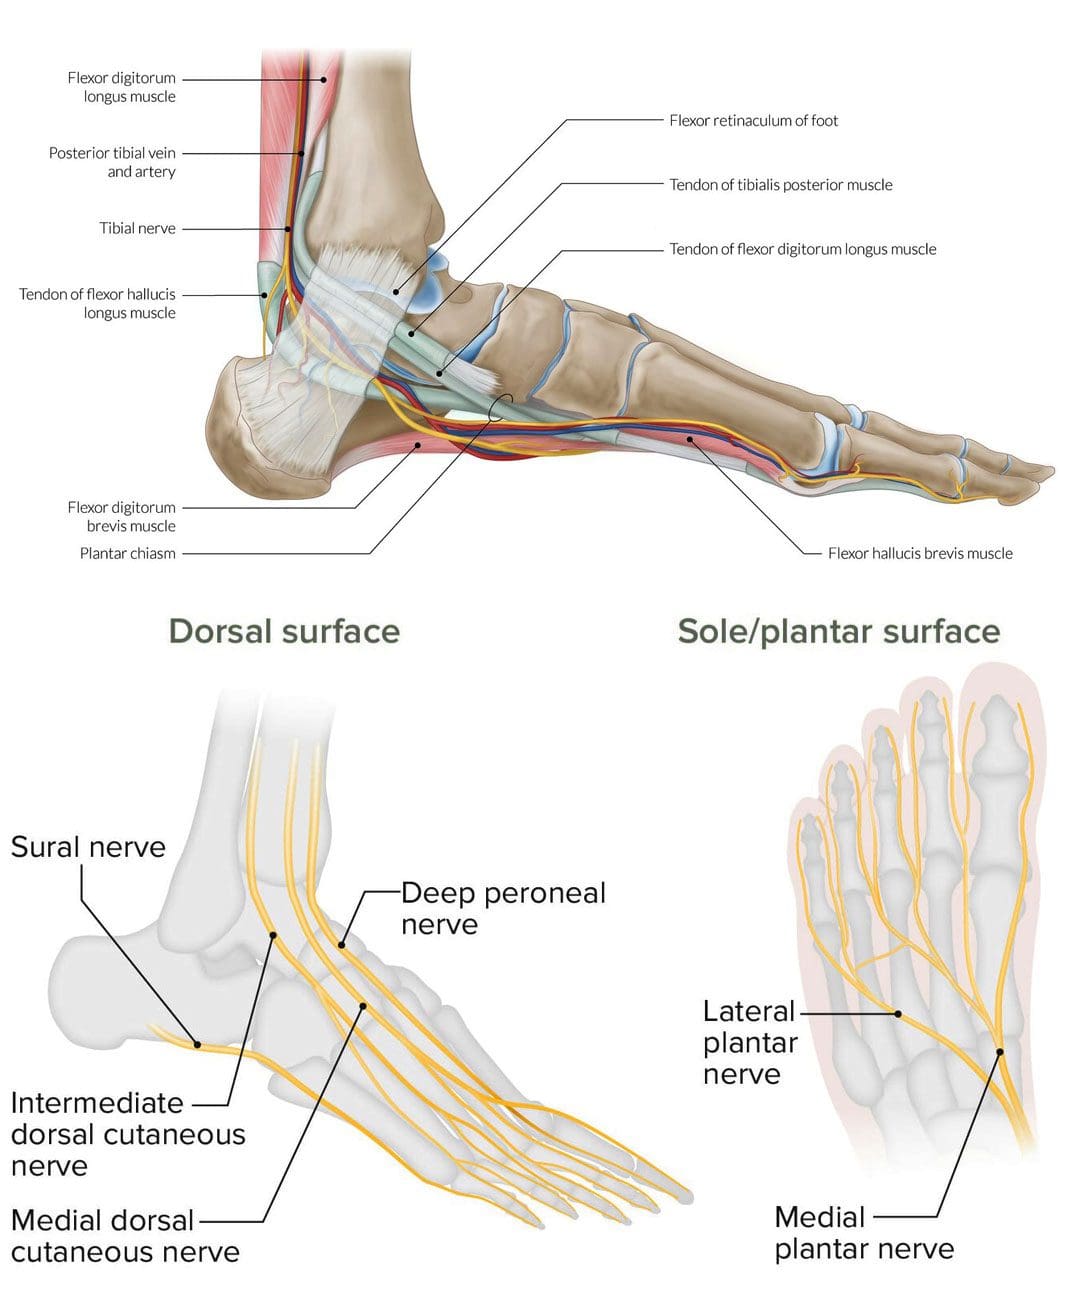

Анатомические фото голеностопного сустава и его суставных поверхностей